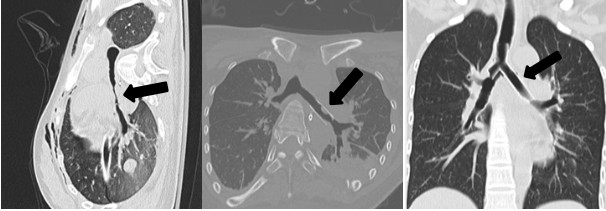

气管支架治疗5例:CT或气管镜明确诊断为软骨环破裂和(或)软化致气管塌陷后,经气管镜置入金属或硅酮支架。1例左主支气管塌陷,置入金属支架1枚,18 d后取出,但管壁仍软化塌陷、脱机困难,予置入Y形硅酮支架,1年后拔出(图 1 A~C),恢复良好。1例隆突上方气管及左主支气管广泛软骨环形破裂、憩室形成,右主支气管开口处软化、塌陷狭窄,置入金属支架1枚,3周后取出(图 2 A~C),恢复良好。1例因左侧气胸、左主支气管塌陷,置入金属支架1枚,术后出现左肺不张,多次经气管镜吸痰治疗,术后2周取出,左肺复张(图 3 A~C)。另2例气管塌陷患者,各置入金属支架1枚,2~3周后取出。5例患者置入支架后均观察到粘痰堵塞,每日予气管镜吸出。5例患者均效果良好,未见支架移位,支架取出后随访6个月以上,未出现气道狭窄。

| A 为左主支气管狭窄;B 为金属支架植入术后;C 为硅酮支架植入术后 图 1 相继置入金属支架、硅酮支架TBI患者1例 |